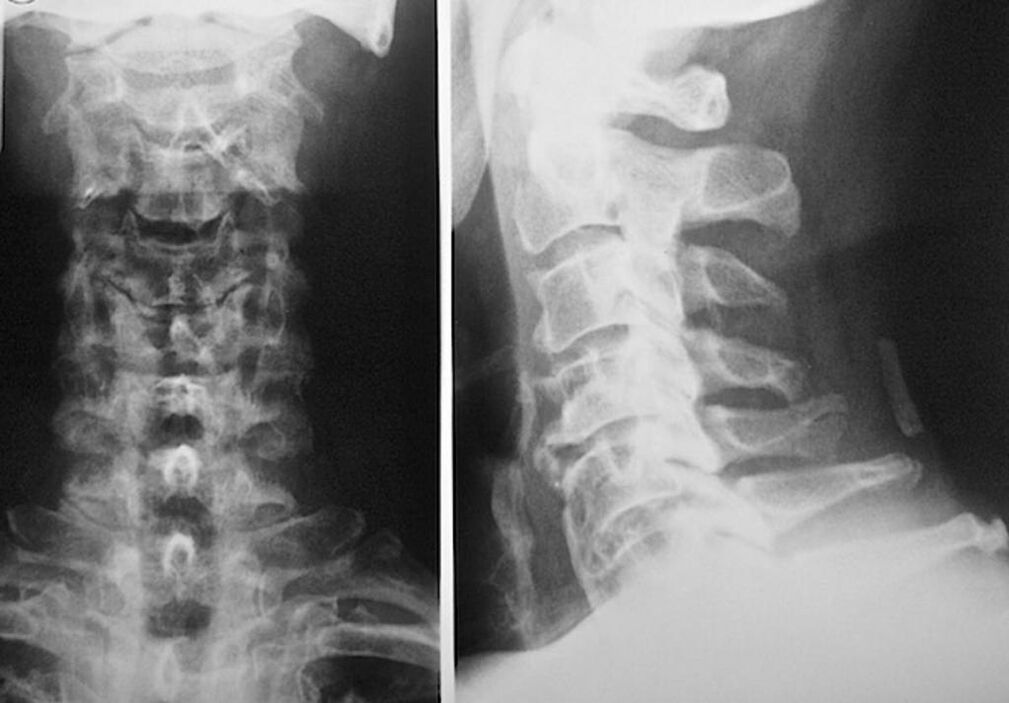

For the diagnosis and accurate assessment of the condition of intervertebral discs, the following research methods are used:

- X-ray.

- computed tomography.

- Magnetic tomography.

- Ultrasonography of the cervical vessels.

Each of them is completely safe for health and poses no threat of overexposure. The diagnosis of osteochondrosis of the cervical vertebrae, whose treatment will be carried out throughout life, can be performed after a simple visual examination. Any orthopedist can easily do this. An exception is the first stage of the disease, when visible pathologies of the cervical region are not noticed.